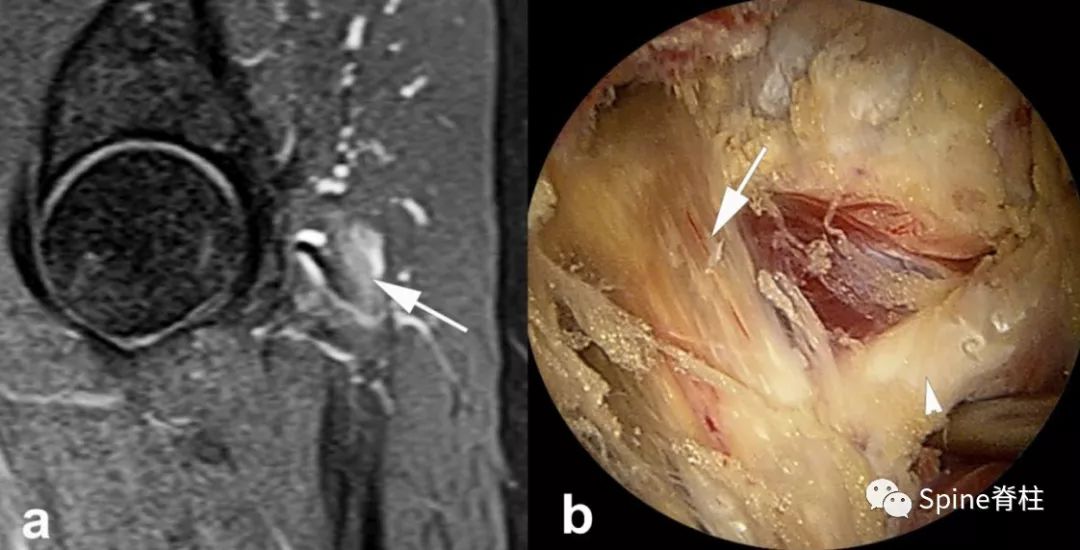

图示:确诊为 LSTV IIb型(具体分型详见: 你注意过腰5椎体的横突吗? ),患者L5神经根右下肢放射痛通过选择性根管造影确诊,增生肥大的横突与骶骨形成的假关节压迫椎间孔外侧远距离处的L5神经。